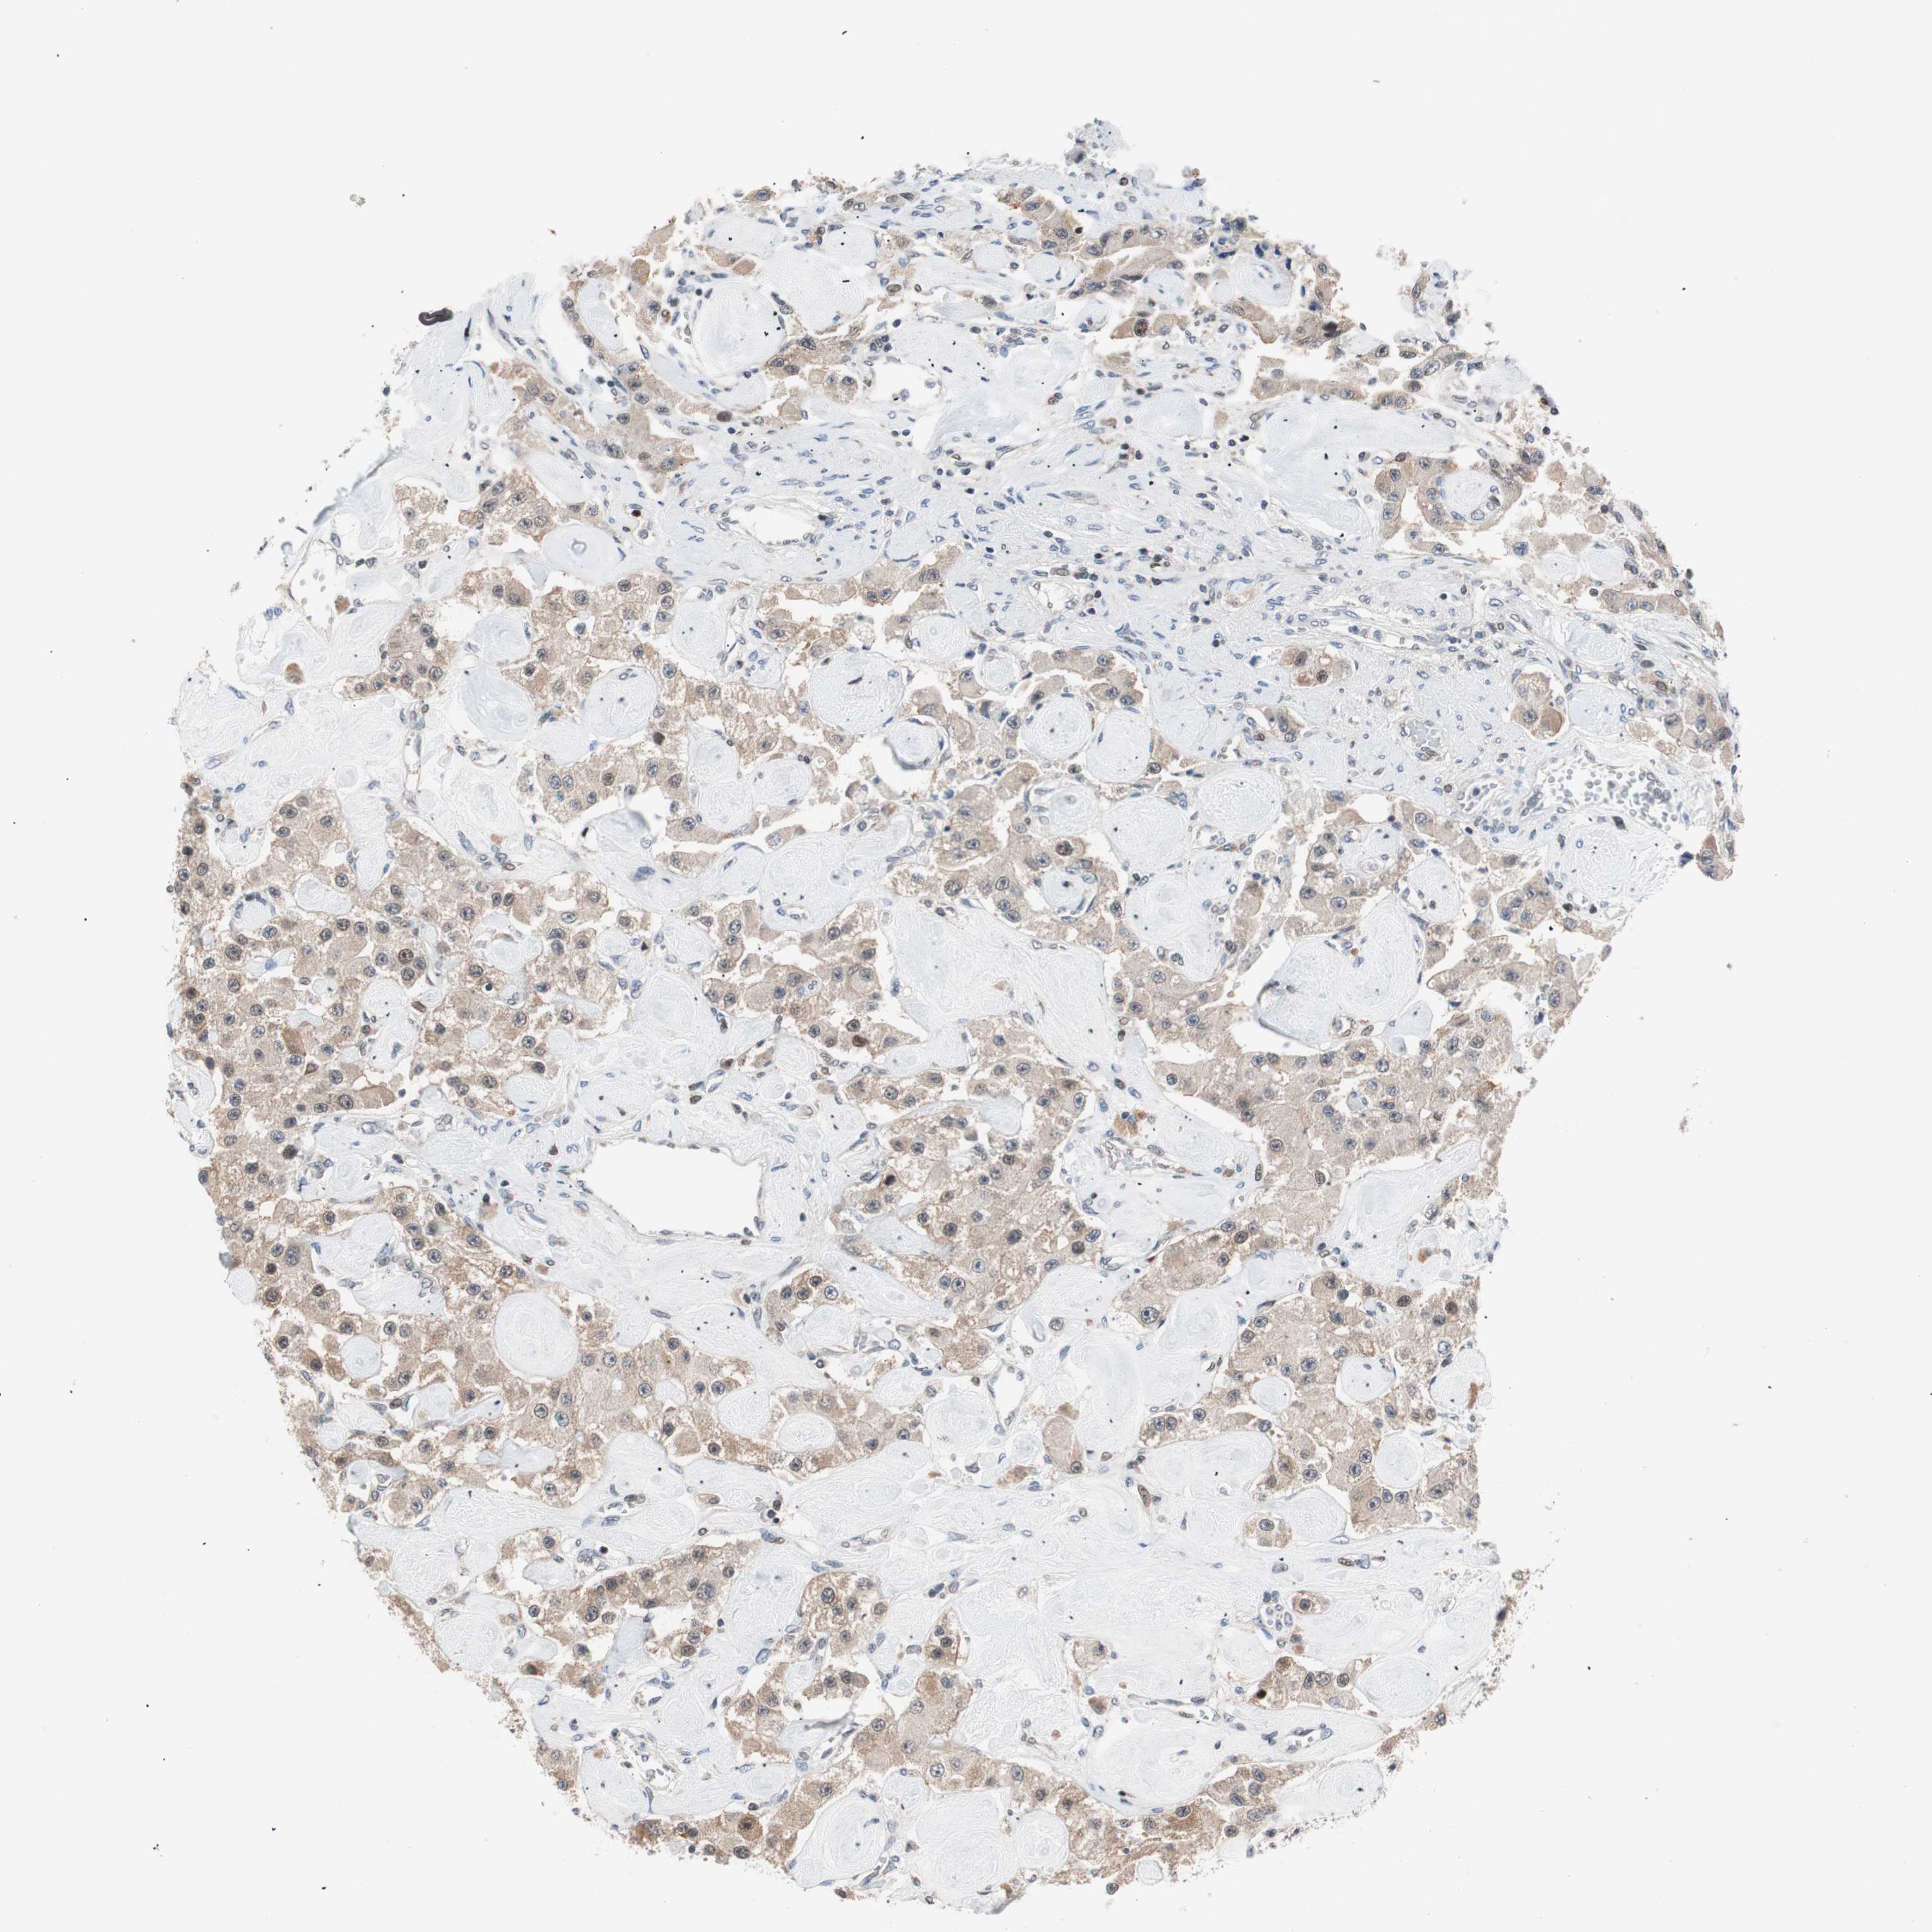

CARCINOID - Protein expressioni

A mouse-over function shows sample information and annotation data. Click on an image to view it in a full screen mode. Samples can be filtered based on level of antibody staining by selecting one or several of the following categories: high, medium, low and not detected. The assay and annotation is described here.

Antibody stainingi

Antibody staining in the annotated cell types in the current human tissue is reported as not detected, low, medium, or high, based on conventional immunohistochemistry profiling in selected tissues. This score is based on the combination of the staining intensity and fraction of stained cells.

Each image is clickable and will lead to virtual microscopy that enables deeper exploration of all samples and also displays staining intensity scores, fraction scores and subcellular localization as well as patient and tissue information for each sample.

Antibody HPA026762

Staining

Medium

Intensity

Moderate

Quantity

75%-25%

Location

Cytoplasmic/membranous

Carcinoid, malignant, NOS